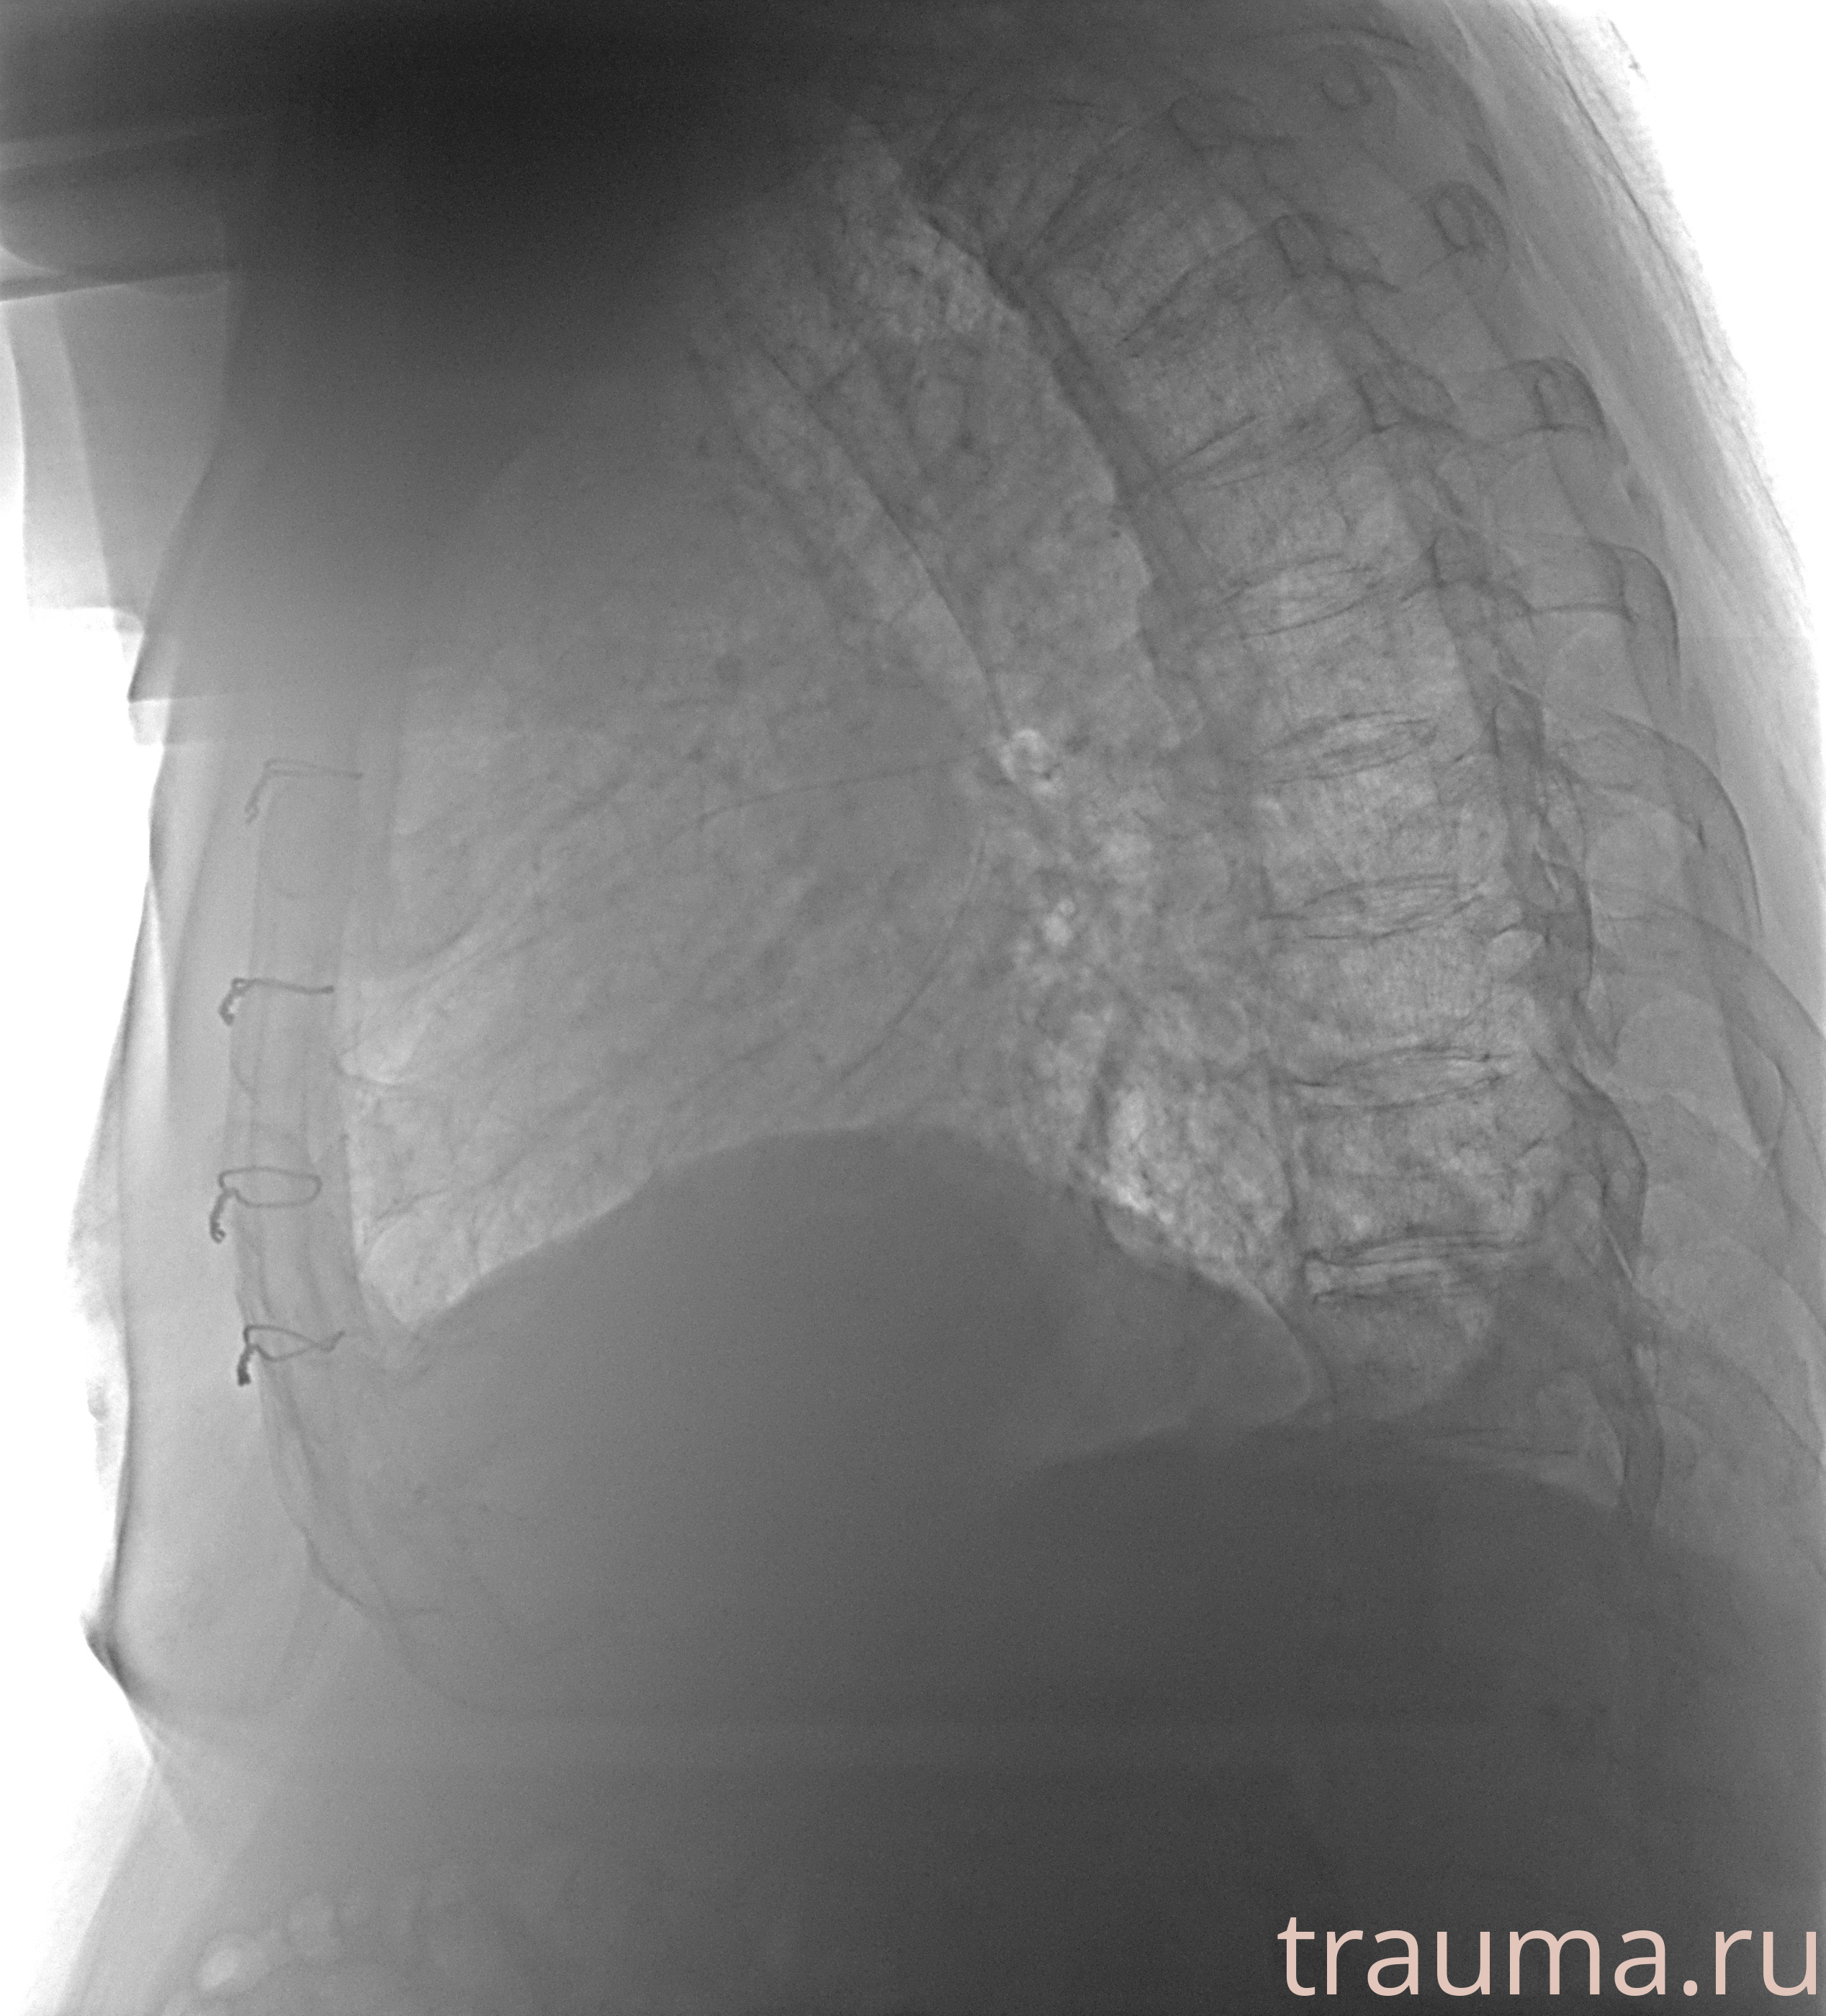

Рентгенограммы

Рентген на дому: по вашему адресу приезжает врач-рентгенолог, травматолог-ортопед с мобильным рентгеновским аппаратом, проводит диагностику травмы или заболевания, делает необходимые рентгенограммы, дает рекомендации по дальнейшему лечению. Получить качественные снимки в домашних условиях возможно благодаря уникальной методике, разработанной МосРентген Центром для института  Склифосовского